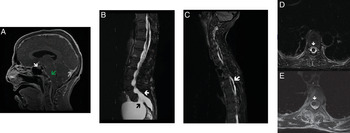

A 48-year-old woman known for Marfan syndrome, with a mechanical valve on anticoagulation, and chronic back pain last treated with lumbar epidural injections 2 years ago presented to a community hospital complaining of severe, non-positional, headaches. She could not recall when she had her last injection. Within hours, her level of consciousness declined precipitously and urgent transfer to our centre was arranged. When she arrived, she was febrile, unable to open her eyes and localised to pain bilaterally (GCS E1V1TM5). CT demonstrated tonsillar herniation, diffuse cerebral sulcal effacement and pseudo-subarachnoid sign. Contrast-enhanced MRI of the brain and spine was ordered to assess for primary differentials of meningitis, venous thromboembolism and spontaneous intracranial hypotension (SIH). This revealed multiple features consistent with SIH (Figure 1A). Imaging also demonstrated known sacral dural ectasia with evidence of newly enlarging meningocele and spinal longitudinal epidural CSF collections (SLECs) (Figure 1B-D). Trendelenburg positioning leads to immediate improvement of her GCS, but gradual elevation of head of bed was not tolerated.

Figure 1: Findings of Intracranial Hypotension with SLECs. (A) Contrast-enhanced MRI of the brain demonstrating multiple features of SIH: enlarged pituitary (white arrow), sagging brainstem (green arrow) and rounding of torcular (grey arrow). (B) Sagittal lumbosacral T2-weighted MRI demonstrating known dural ectasia (white arrow) and enlarging S1 meningocele (black arrow). (C) Sagittal T2 MRI demonstrating thoracic SLECs (white arrow). (D) Axial T2-weighted MRI at T8 level demonstrates a SLEC (white arrow). (E) Following EBP, clinical improvement and resolution of the SLEC were seen (white arrow) with unrelated flow artefact lateral to cord.

In the context of active anticoagulation, we relied on the presence of SLECs to hypothesise that the dural defect lays at, or medial to, the neural foramen and would therefore likely be responsive to epidural blood patch (EBP). Anticoagulation was briefly paused to facilitate this procedure, which lead to sustained clinical improvement and resolution of SLECs (Figure 1E). The patient was discharged home headache-free 10 days after initial presentation.

Approximately 15% of patients with SIH suffer from underlying connective tissue disorders such as Marfan syndrome, and up to 94% are initially misdiagnosed. Reference Mokri, Maher and Sencakova1,Reference Schievink2 CSF leaks contributing to SIH have been classified into four subtypes: I. Ventral dural tear, II. Proximal nerve root sleeve dehiscence, III. CSF-venous fistula or IV. Extravasation from distal root sleeve (e.g. into enlarging meningocele). Reference Schievink, Maya and Jean-Pierre3 In our patient, it was unclear whether the cause was a ventral tear that could respond to EBP (type I/II) or tear within her meningocele sleeve (type IV), which would require surgical repair (Figure 1B). Although invasive myelography is often pursued, the presence of SLECs strongly favours a type I/II tear responsive to EBP. Reference Farb, Nicholson and Peng4 In order to minimise pauses in anticoagulation, we elected to pursue upfront EBP based on non-invasive imaging. Symptom resolution following this procedure strongly supports our pre-intervention hypothesis.